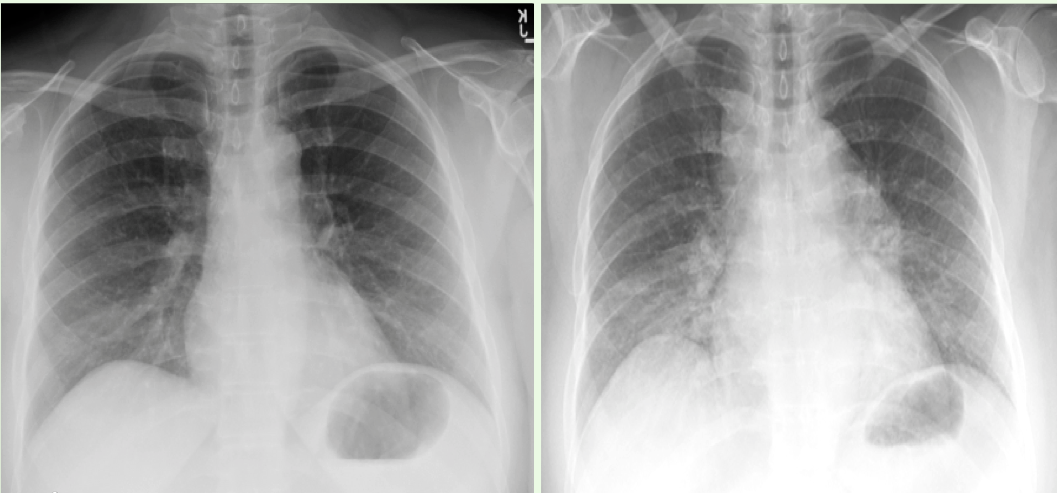

What are key differences to notice in the XRAY on the right vs. the left?

Left: • Normal, there is not any hilar inflammation etc. Right: • we see bilateral perihilar infiltrates with increased opacity in the lateral aspect of both lungs